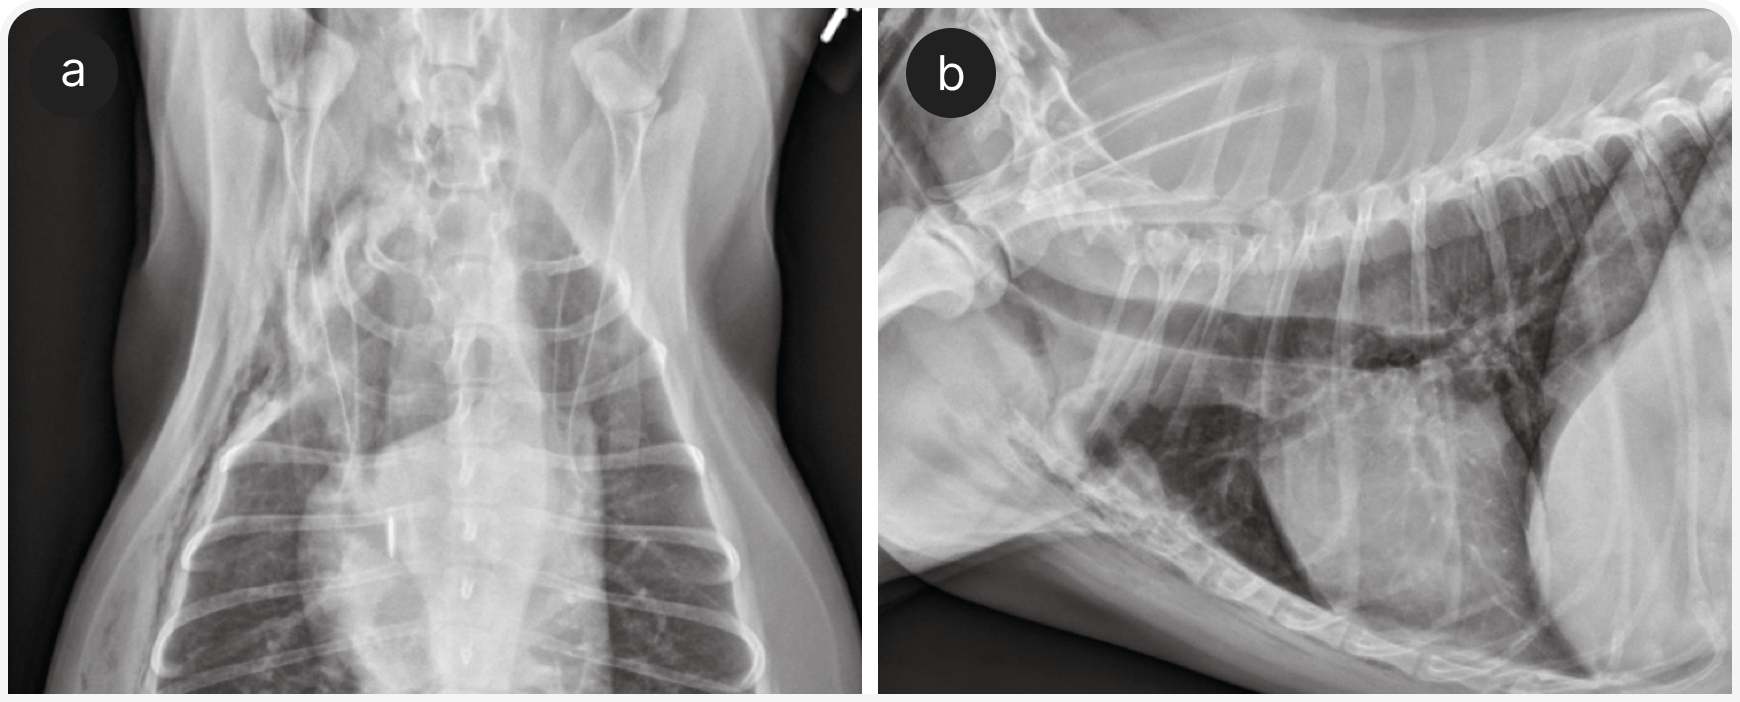

Этим пациентам могут быть полезны ингаляции кислорода и бронходилататоры, такие как тербуталин; однако у собак с подозрением на серьезные заболевания сердца следует соблюдать осторожность, так как тербуталин может увеличить частоту сердечных сокращений. После стабилизации рекомендуется провести рентгенографию органов грудной клетки для выявления картины бронхиального или бронхоинтерстициального поражения (Рисунок 2), хотя диагностическая чувствительность рентгенографии при заболеваниях бронхов у собак относительно низкая (2).

Рентгенография органов грудной клетки — основной метод диагностики у собак с заболеваниями легочной паренхимы (Рисунок 4), так же используется «прикроватное» УЗИ (POCUS), если это возможно, и эхокардиографией, если в списке дифференциальной диагностики высока вероятность заболевания сердца (Рисунок 5). В ожидании первоначального диагностического обследования можно рекомендовать компьютерную томографию органов грудной клетки и эндотрахеальный лаваж. По их результатам решают, следует ли ограничить лечение ингаляцией кислорода или нужно добавить антибиотики, диуретики, стероиды, бронходилататоры.